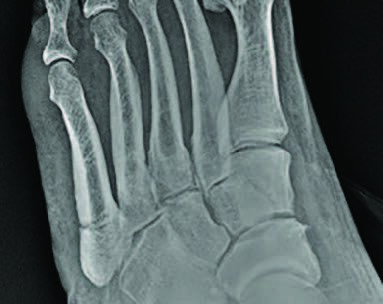

Fifth metatarsal fractures have been classified by Lawrence and Dameron based on the location of the fracture.1 Zone 1 fractures include the proximal tuberosity of the fifth metatarsal, referred to as avulsion fractures or pseudo-Jones fractures (see first photo above).